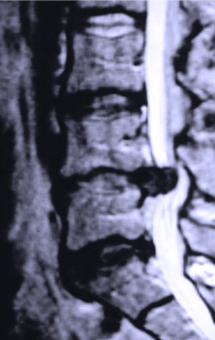

Common spinal problems include disc herniation, spinal stenosis (arthritic narrowing), spondylolisthesis, (slippage of the vertebrae) and bone spurs can cause a wide range of symptoms from pain, numbness, weakness, gait disturbance and in severe, but rare, cases may cause paralysis, and loss of bowel, bladder and sexual function.

Dr Johnson has a vast understanding of these complex problems and their management is an essential part of his daily practice and represents the majority of the 6000 spinal procedures he has performed in his career. Previous surgery or “failed back surgery” is also a challenging problem that is also a large part of Dr Johnson’s practice that he developed experience often taking on some of the most challenging cases.